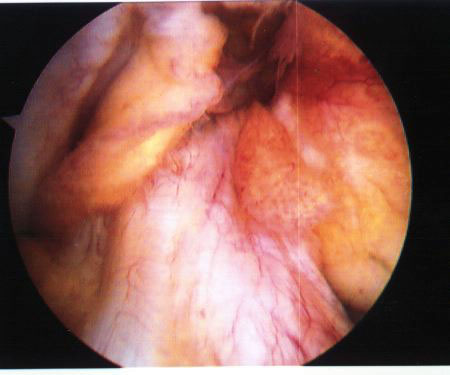

レントゲンは骨折有無の確認に有用ですが、靱帯は写りません。また、関節鏡(内視鏡)検査は最も有用で確実な診断が得られますが、皮膚切開、麻酔など手術手技に準じた侵襲があります。ACL単独での損傷例は少なく、内側側副靱帯損傷や半月板損傷を合併している場合が多いのが特徴です。

ACL軽度損傷の関節鏡写真。靱帯は弛緩しているものの、形態は保たれている。